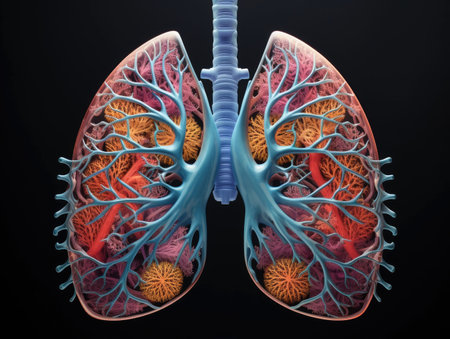

Anatomical model of human lungs featuring vivid colors and intricate patterns, highlighting the complexity of the respiratory system in an educational display.

Detailed 3D-printed lung model on black surface. Intricate bronchial trees, alveoli, red/blue arteries/veins. Cross-section shows pleural structures. Angled lighting, soft shadows. Blurred background: robotic arm, holographic airflow. Futuristic research lab. Anatomical precision.

Lungs of human, 3D illustration. The structure of the human lungs.

This artwork presents a vivid representation of human lungs, highlighting their complex structure and respiratory systems branching pathways.